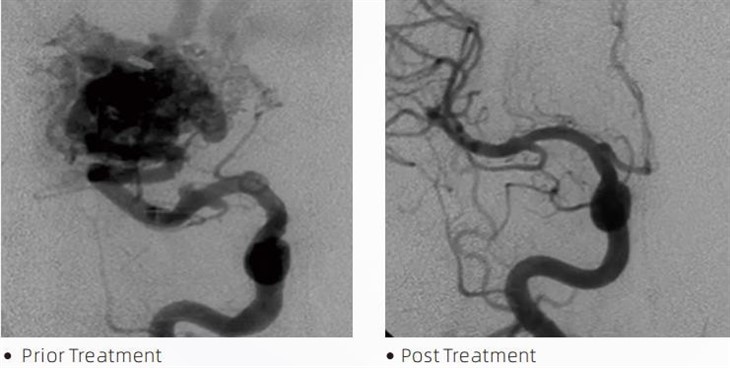

LaveMTLa colle embolique est un dispositif médical utilisé par les neuroradiologues interventionnels lors d'interventions mini-invasives pour traiter des affections telles que les anévrismes cérébraux, les malformations artério-veineuses et les tumeurs. La colle embolique Lava offre de multiples avantages aux professionnels de la santé et aux patients en termes de sécurité, de facilité d'utilisation et d'efficacité. La lave est capable de sceller les vaisseaux sanguins rapidement et efficacement. Le processus consiste à injecter la colle directement dans le vaisseau ciblé, où elle polymérise et durcit en une masse semblable à un plâtre qui remplit l'anévrisme ou la malformation. Ensuite, il coupe efficacement le flux sanguin vers la lésion, l'empêchant de se rompre et réduisant le risque de dommages permanents ou d'accident vasculaire cérébral. La lave comprend la lave-12, la lave-18 et la lave-34. Chaque formulation est conçue pour répondre à des besoins cliniques spécifiques. Lava-18 est une formulation standard pour une utilisation générale. Lava-34 est une colle à haute viscosité pour les navires à haut débit. Alors que Lava-12 a une viscosité plus faible et est plus fluide, permettant des microvaisseaux distaux. Avec ces options, les neuroradiologues interventionnels peuvent choisir les formulations Lava appropriées pour garantir des résultats optimaux. L'une des caractéristiques les plus remarquables de Lava est ses propriétés non adhésives. Cette substance est spécialement formulée pour rester stable jusqu'à ce qu'elle atteigne la zone ciblée. Cette caractéristique signifie que la colle embolique Lava peut être placée avec précision dans l'artère et y rester sans coller ni se lier aux tissus environnants.